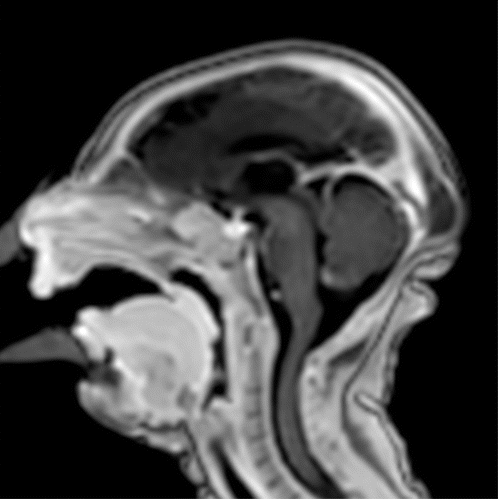

Though much of the concern in the media regarding the toxic effects of Zika virus has focused on brain findings of microcephaly, the researchers noted that there are a variety of brain abnormalities that can be found in fetuses exposed to the virus, including gray and white matter volume loss, brainstem abnormalities, calcifications and a condition called ventriculomegaly, where the ventricles, or fluid filled spaces in the brain, are enlarged. Some babies infected by Zika may not have a small head size if the ventricles remain excessively enlarged.

Ninety-four percent of the confirmed Zika group and 79 percent of the presumed Zika group had abnormalities of the corpus callosum, which is a large nerve fiber bundle that allows communication between the left and right hemispheres of the brain. All but one had cortical migrational abnormalities, meaning the neurons did not travel to their proper destination in the brain.

Intracranial calcifications were present in almost all of the neonates, most commonly found at the gray-white junction of the brain. All of the babies exhibited reduced tissue volume in their brains. All patients showed varying abnormalities in cortical development.

The babies’ skulls frequently had a collapsed appearance with overlapping sutures and redundant skin folds. The researchers believe the unusual appearance of the skull is due to a combination of the small brain as it develops, but also a result of what at some point was likely a larger head size — due to ventriculomegaly — that then decompresses, and/or brain atrophy, giving the skull the collapsed shape.